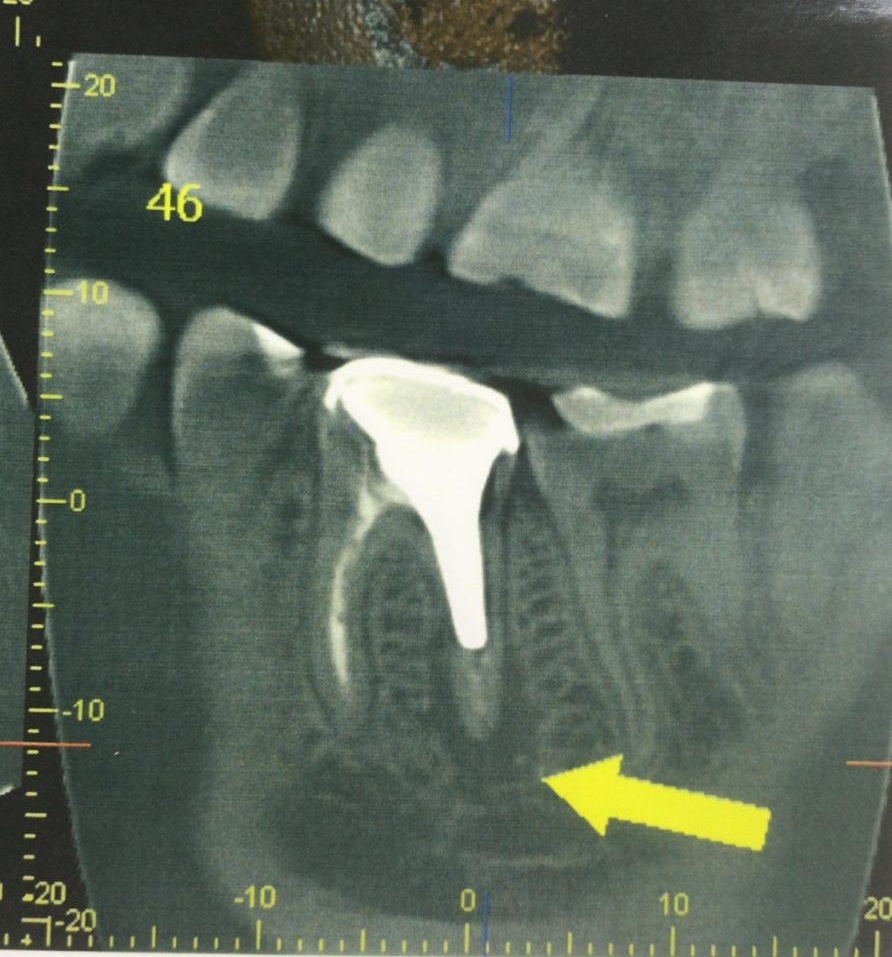

Зуб 46 разрушен очень сильно, и больше не может выполнять функции.

Протезировать, а тем более реставрировать его бесполезно и бессмысленно. Принято решение заменить его имплантом Strauman SLActive (система входит в топ 5 по миру).

46 — трещина в медиальном корне — причина титанов штифт установленный под неправильным углом. Как следствие трещины переодические ноющие боли после приема пищи.

Что сделали: атравматичное удаление, установка импланта Straumann BLT 4.1x10mm, формирователь, костная пластика, пластика слизистой, APRF. Операцию провели одномоментно — сохранили объём кости, слизистой.